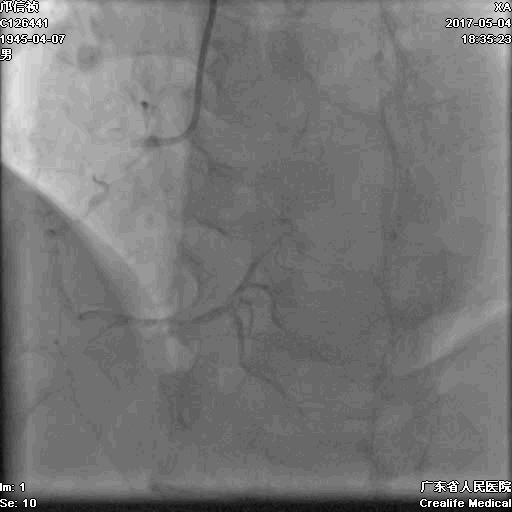

冠脉造影

基本资料

Syntax score 37.5

首先:IVUS指导下干预LAD

4.0mm*13mm药物支架